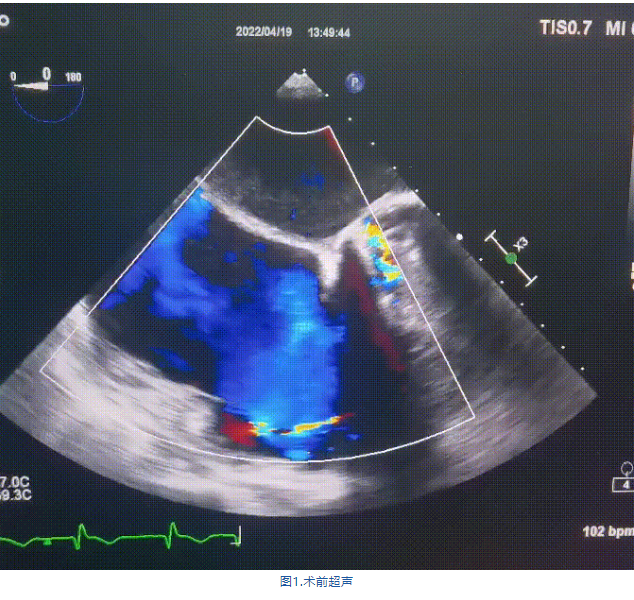

此次手術(shù)在全麻下進(jìn)行,采用經(jīng)右側(cè)頸靜脈入路。術(shù)中在經(jīng)食道超聲和DSA的指引下多個(gè)維度精細(xì)調(diào)整輸送器角度,在達(dá)到正確位置后,逐步釋放瓣膜錨定裝置和盤片,最終完成瓣膜植入。術(shù)后患者右房壓明顯下降,術(shù)后超聲提示人工三尖瓣同軸性良好,瓣架固定牢靠,無反流和瓣周漏,血壓術(shù)后即刻上升20mmHg左右,手術(shù)后監(jiān)護(hù)室順利拔除氣管插管,3天后恢復(fù)良好,予以出院。